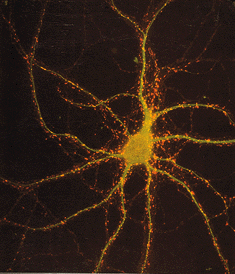

Here are some images of the neuron system in the brain

The differences between the brain from 1 month age till 1 year.